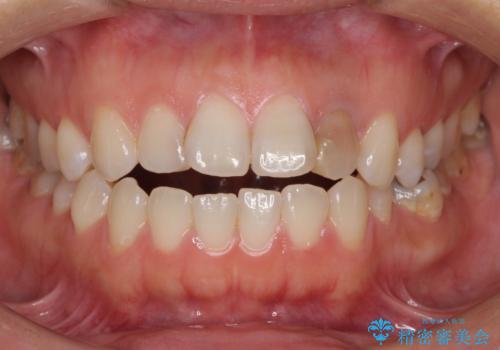

開咬と変色した前歯 インビザライン矯正とオールセラミッククラウン治療

- 前歯の開咬と失活により変色した前歯を気にして来院された患者様です。

開咬の治療は、前歯を閉じるように引っ張り出すよりも、上下臼歯を圧下(骨内にめり込ませる)させることで進める方が長期的に安定した歯列を維持できます。

インビザラインは臼歯の圧下を効果的に行えるため、インビザラインを用いて矯正治療を行うこととしました。

矯正治療が概ね終了した時点で前歯をオールセラミッククラウンにて補綴治療を行い、その後インビザラインにて細かい部分を仕上げていくことしました。